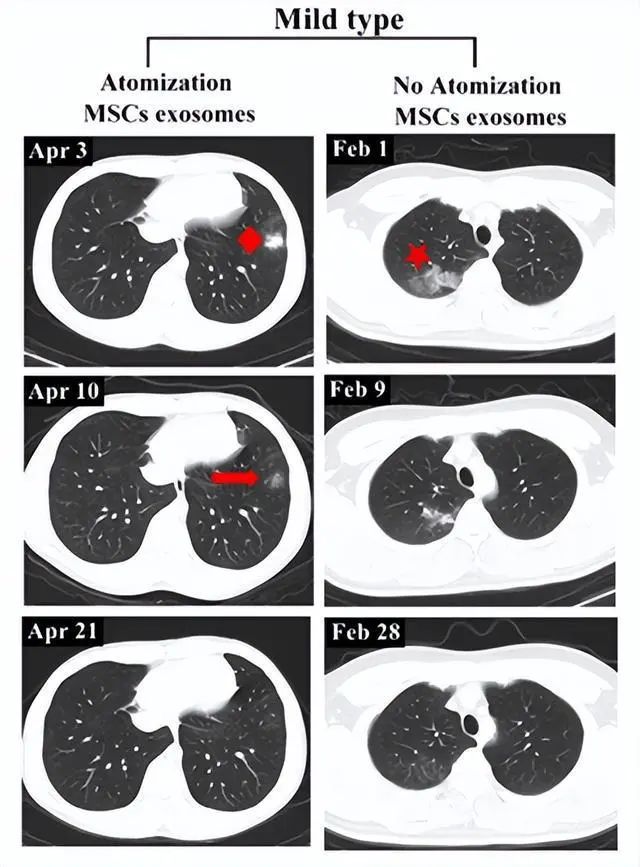

轻度病例前后影像变化:以患者6为例,2020年4月3日,该患者第一次CT扫描显示左肺下叶外有孤立结节,4月4日,患者接受外泌体雾化治疗,4月10日,第二次CT检查显示左肺下叶结节密度明显降低,大小也缩小,4月21日,第三次CT检查,左下肺病灶完全吸收,从发现结节到完全吸收肺部病变所需的时间为18天。

相比之下,另一例患者(轻度病例,无雾化治疗)类似肺部病变的吸收时间为27天。

▲左:患者6;右:无外泌体雾化治疗的轻度病例